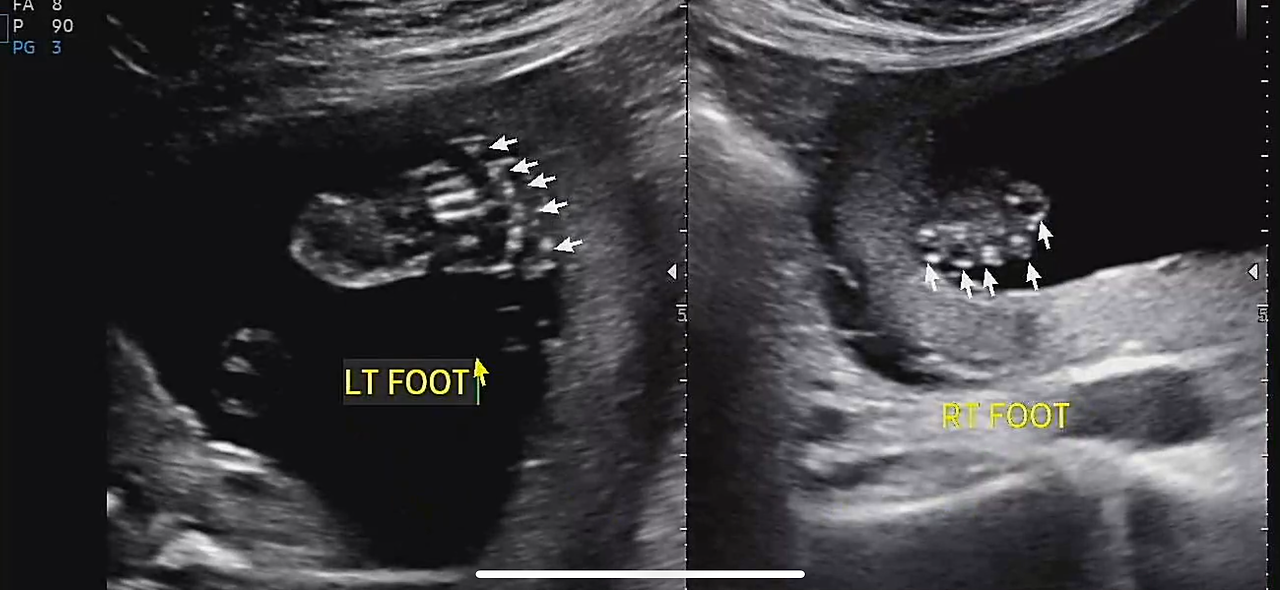

정밀 초음파는 생각보다 오래 걸렸다.

30분 가까이 이어진 검사 동안

손가락, 발가락, 귀, 콧구멍까지

아이는 하나하나 자세히 확인되었다.

22주 정밀초음파